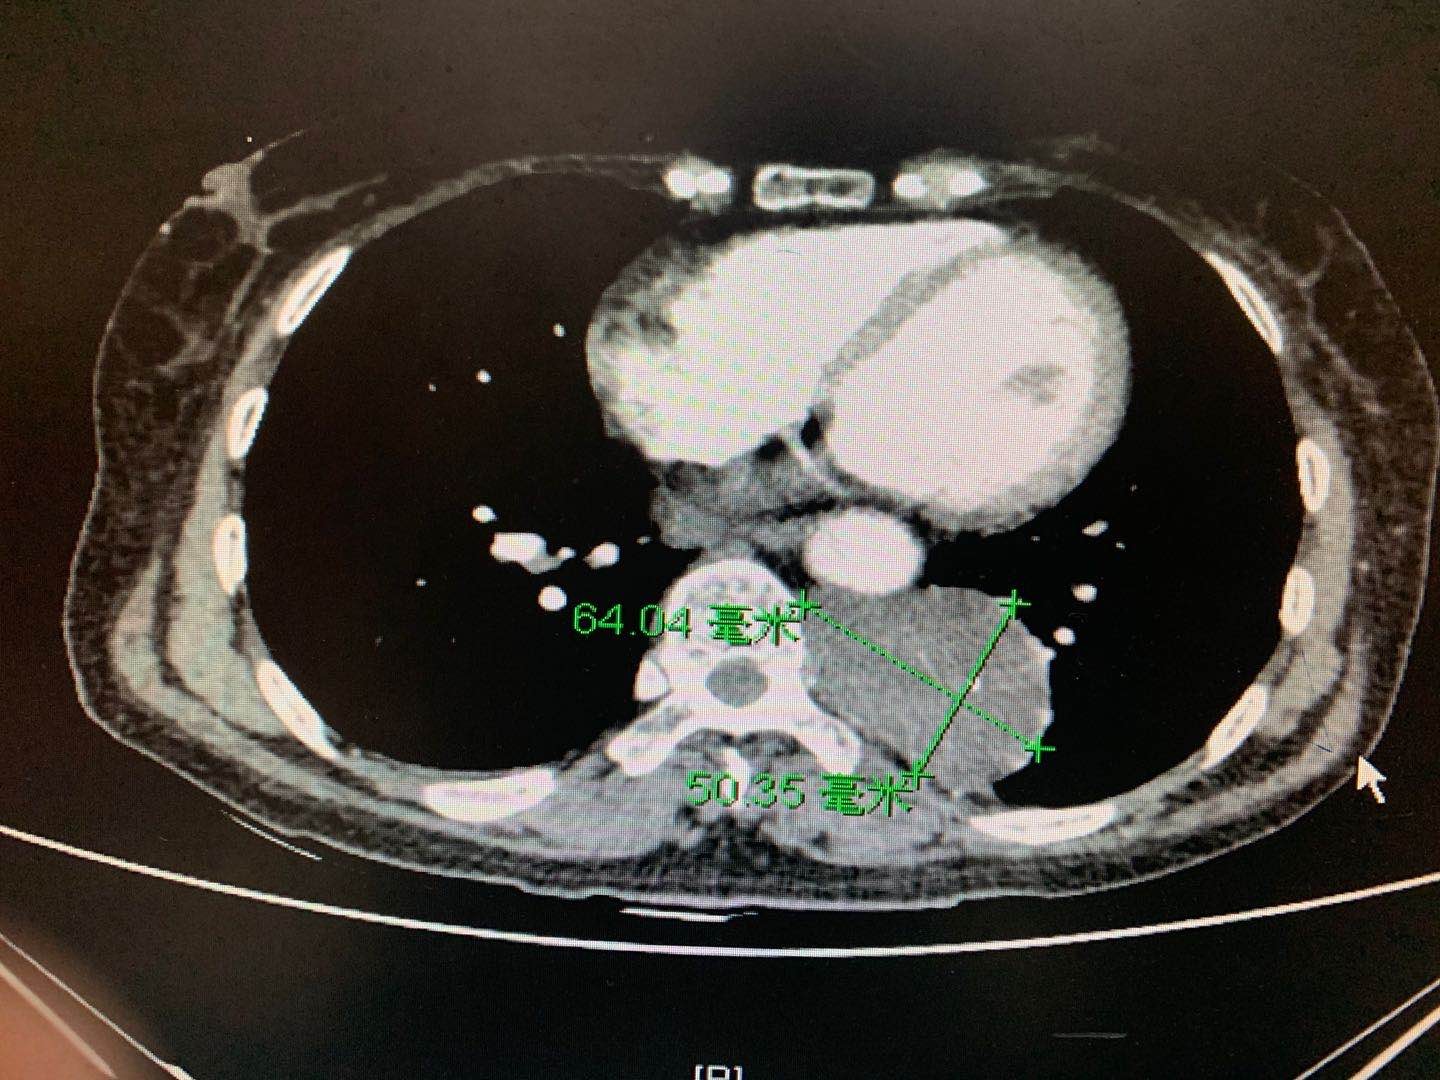

近日,徐醫(yī)附院心胸外科王國祥、侯永波、張虎團隊在麻醉科及手術室的幫助下,成功為一例較大縱膈腫瘤患者實施了達芬奇機器人輔助行胸腔鏡下手術切除。該縱膈腫瘤位于胸主動脈和椎體之間,6.4cm×5.0cm大小,且和椎間神經(jīng)與血管相連。手術團隊通過充分發(fā)揮手術機器人的優(yōu)勢,在狹小的空間里,在10倍放大的視野下實施精準操作,不僅成功地完整地切除了腫瘤,還避免了對周圍組織的損傷。